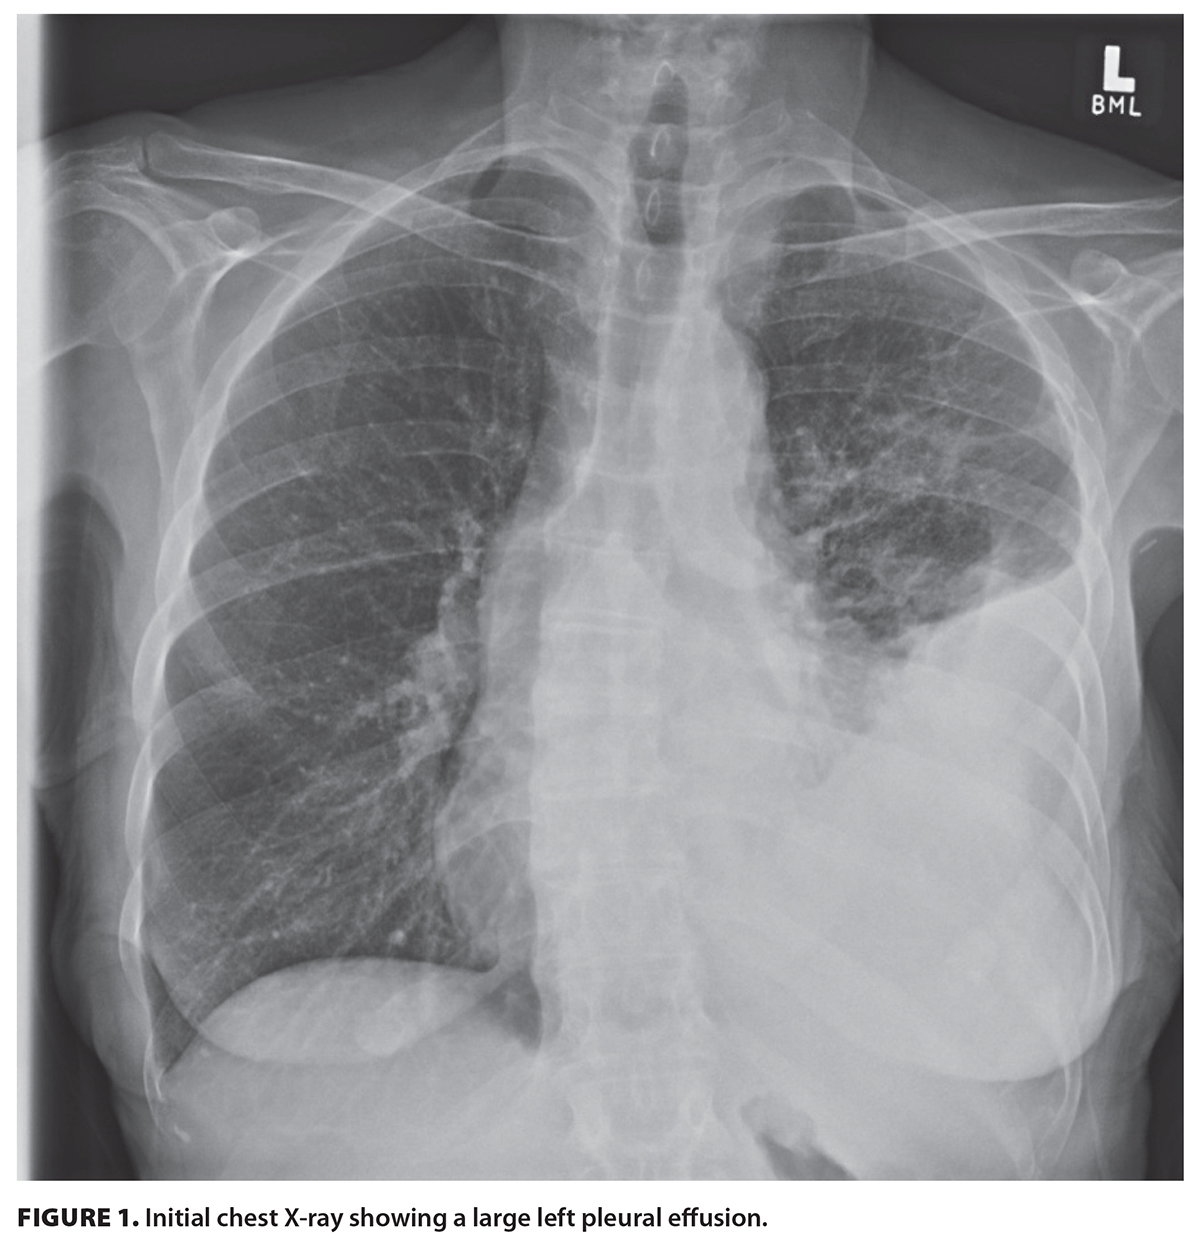

Upon presentation to a Canadian emergency department, the woman was hypoxic and minimally ambulatory. Chest X-ray showed a large left pleural effusion [Figure 1]. CT imaging showed a large left pleural effusion, multiple spiculated nodules in the left lung, mediastinal lymphadenopathy, and liver lesions [Figure 2]. Tumor markers CEA, CA 15-3, CA 19-9, and CA-125 were elevated.